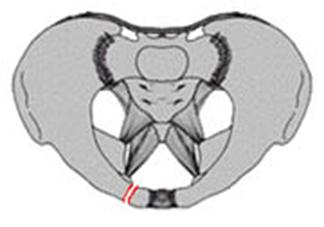

TRAUMATISMELE PELVIENE

Traumatism

pelvian Hemipelviectomie dreapta posttraumatica

Banda de stabilizare Dallas Fractura de bazin. Radiografie in

incidenta AP

Inaintea

aplicarii benzii de stabilizare Dallas

Fractura de bazin

. Radiografie in incidenta AP Fractura de spina

iliaca antero-superioara

Dupa aplicarea benzii de stabilizare Dallas prin avulsie. - Stabila -